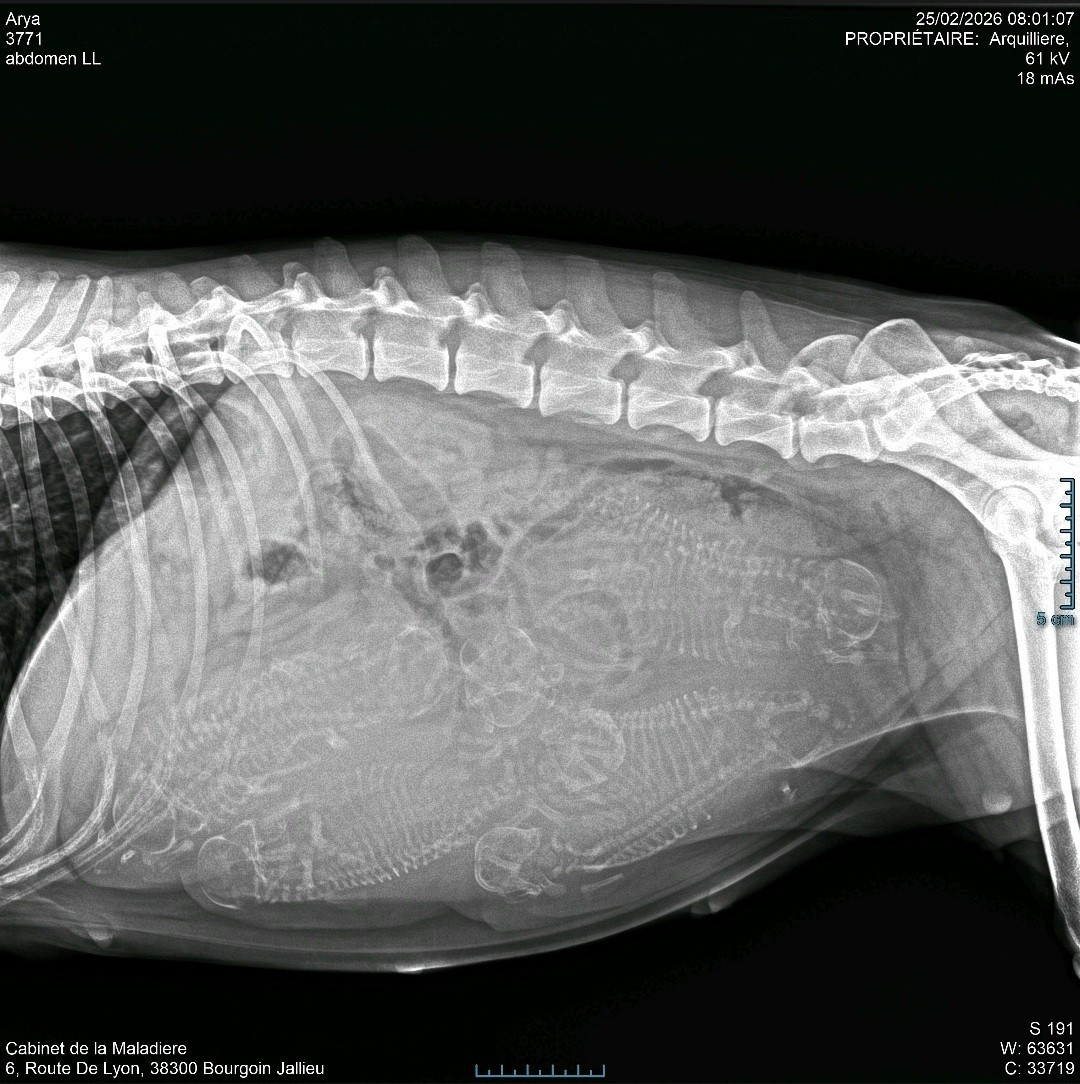

Alors à votre avis combien de bb se cachent dans mon ventre ?

La radio de gestation faite ce mercredi 25 février nous avons montré 8 petits crânes...